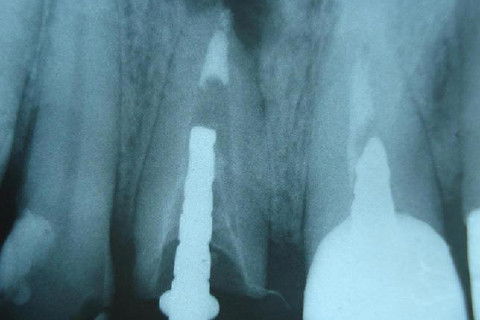

Constatação de travamento por meio radiográfico

Paciente apresentou-se com elemento 11 contendo  retentor intra-radicular insatisfatório sobre tratamento endodôntico na mesma condição. Ao exame radiográfico pôde ser diagnosticada lesão periapical. Foi proposta e executada a remoção da coroa metalocerâmica e núcleo metálico fundido seguido de retratamento endodôntico cumprindo-se os princípios da terapia desde a cirurgia de acesso à obturação. Para tanto, optou-se pela técnica de moldagem prévia do cone de guta-percha empregando calor como uma variação da técnica de condensação lateral. pela dificuldade de travamento que o conduto apresentou por sua amplitude, além da preocupação pelo vedamento do terço apical.

Ao final, obteve-se sucesso endodôntico por meio de um selamento hermético, um travamento ideal utilizando a moldagem apical em um conduto amplos impedindo infiltração apical e permitindo uma visão tridimensional dos canais radiculares. A técnica é de simples execução, não necessitando de instrumental específico, porém requer habilidade clínica e conhecimento.